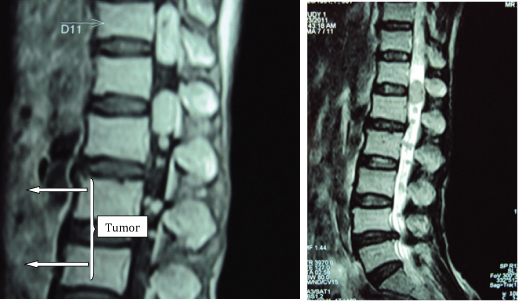

There were 13 swellings noted scattered all over the patient’s body. The various sites being – right distal forearm medially, right cheek, left arm distally on the medial aspect, proximal to the right lateral malleolus, distal to the left knee joint, proximal to the insertion of tendoachilles on the left side [Table/Fig-5], right lumbar region of abdominal wall, left thigh medially and posteriorly each, right gluteal region, 2 over the paravertebral region and left leg anteromedially proximal to the medial malleolus. The patient underwent an Magnetic Resonance Imaging (MRI) of the lumbar spine and screening of whole spine which showed abnormal lesions in the intradural extra-medullary compartment of the spinal canal at cervical, dorso-lumbar and lumbar levels, the largest at L1 and L2 levels [Table/Fig-6a,b]. MRI brain was normal. The Electromyography-Nerve Conduction Velocity (EMG-NCV) was also normal. She was given a conservative trial with analgesic and anti-inflammatory medications, but when symptoms persisted she was operated upon for the lumbar spine swellings.

MRI showing T1W and T2W images of the lumbosacral spine showing the tumour.